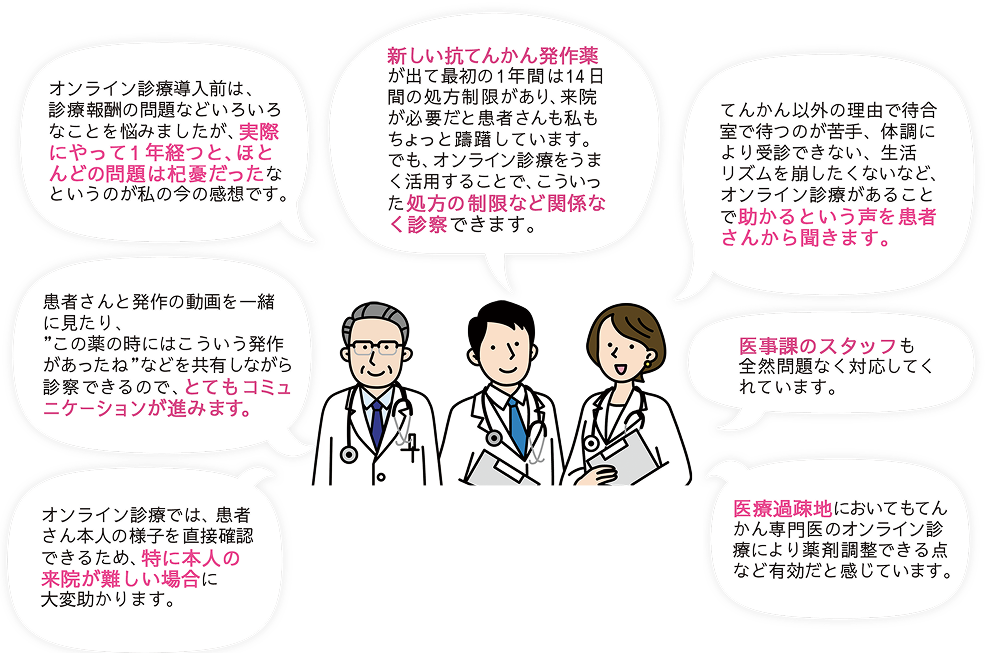

ご利用医師の声(1)

オンライン診療導入前は、診療報酬の問題などいろいろなことを悩みましたが、実際にやって1年経つと、ほとんどの問題は杞憂だったなというのが私の今の感想です。

ご利用医師の声(2)

新しい抗てんかん発作薬が出て最初の1年間は14日間の処方制限があり、来院が必要だと患者さんも私もちょっと躊躇しています。

でも、オンライン診療をうまく活用することで、こういった処方の制限など関係なく診察できます。

ご利用医師の声(3)

てんかん以外の理由で待合室で待つのが苦手、体調により受診できない、生活リズムを崩したくないなど、オンライン診療があることで

ご利用医師の声(4)

患者さんと発作の動画を一緒に見たり、”この薬の時にはこういう発作があったね” などを共有しながら診察できるので、とてもコミュニケーションが進みます。

ご利用医師の声(5)

医事課のスタッフも全然問題なく対応してくれています。

ご利用医師の声(6)

オンライン診療では、患者さん本人の様子を直接確認できるため、特に本人の来院が難しい場合に大変助かります。

ご利用医師の声(7)

医療過疎地においてもてんかん専⾨医のオンライン診療により薬剤調整できる点など有効だと感じています。